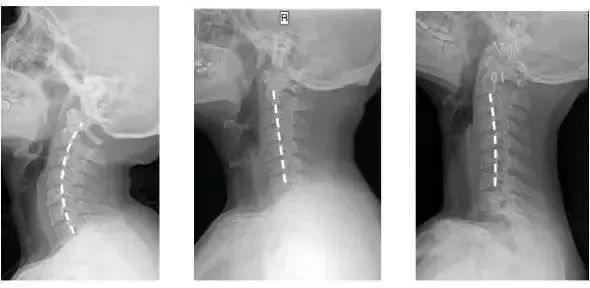

人正常的颈椎是有弧度的

大约是前凸30-45°

但随着颈椎长时间承受着巨大压力

过于疲劳状态

于是弧度就

逐渐退化 变直 甚至 反弓

第一张为正常生理曲度,第二张曲度变直,第三张是反向弯曲

前凸的颈椎曲度被改变

结果就是引发椎间盘突出

造成对血管和神经的压迫

肩膀和脖子容易酸痛僵硬

这已是颈椎病的初期症状